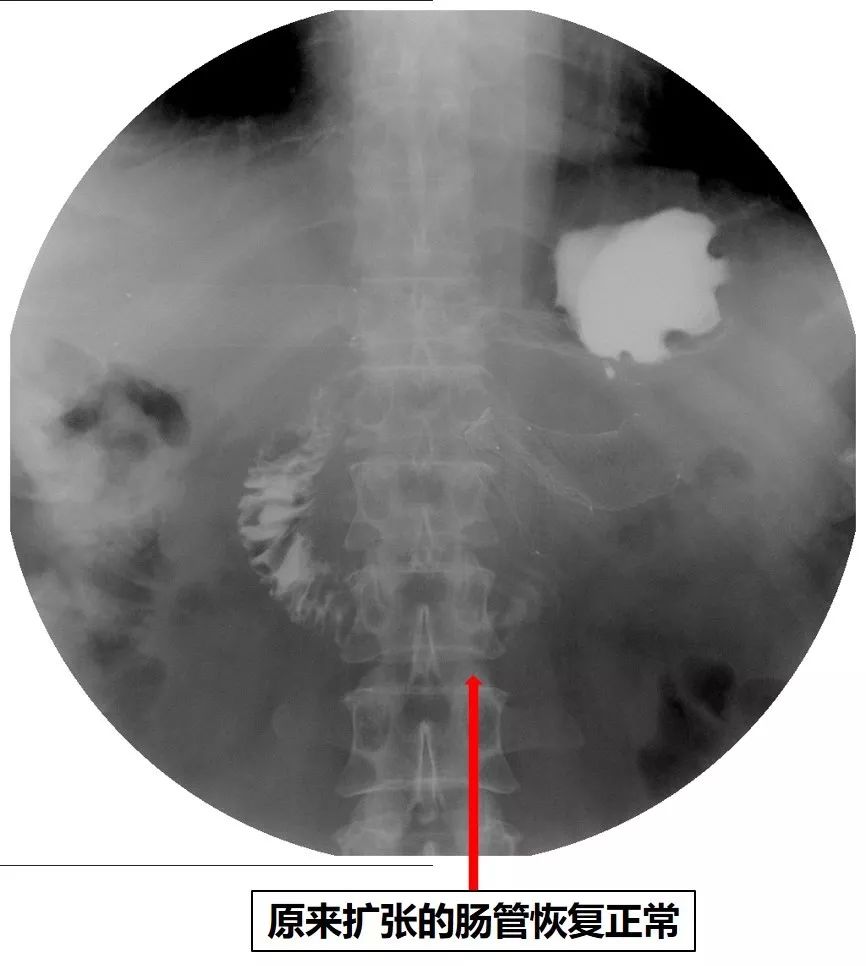

2018年9月底,患者恶心、呕吐症状再次加重,呕吐物为胃内容物,不能进食水,伴反酸、烧心,为进一步治疗来诊。X线腹部平片未见肠梗阻。上消化道造影检查见胃排空障碍,结合之前的内镜检查结果,考虑胃流出道梗阻(图16)。

图16 上消化道造影见胃排空障碍,流出道狭窄